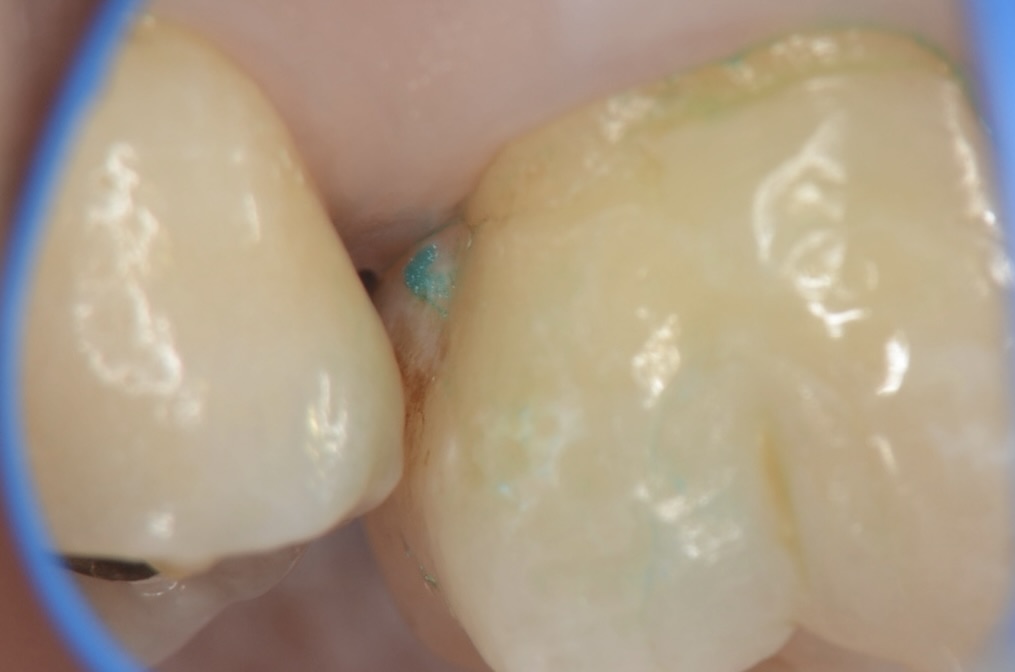

7番近心 頬側から見る

ホリゾンタルスロットテクニックにて横から虫歯を取り除きます。歯の角の部分を残すと強度を保てます。 -

7番近心 口蓋側から見る

トンネルが口蓋側まで貫通しています。 -